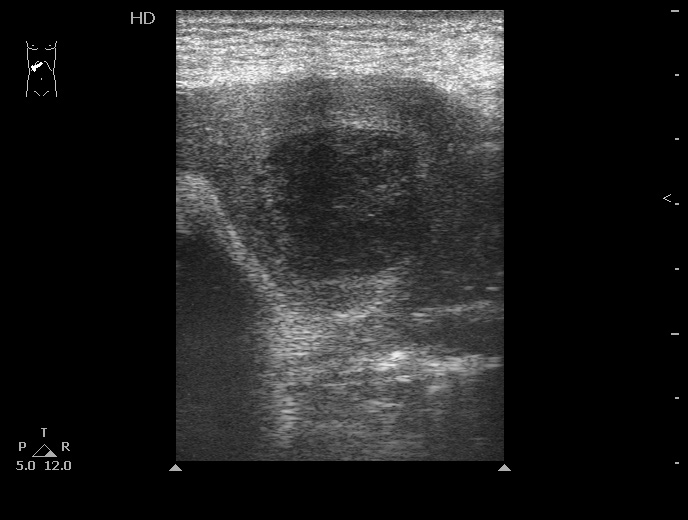

06-12-05-105726_KAZACHENKO-.jpg

06-12-05-105726_KAZACHENKO-.jpg (49.5 КБ) 1487 просмотров

Типичная картина ##1-4:

Гипоэхогенное неоднородное округлое образование, окруженное эхогенным "демаркационным валом"

измененной паренхимы печени.